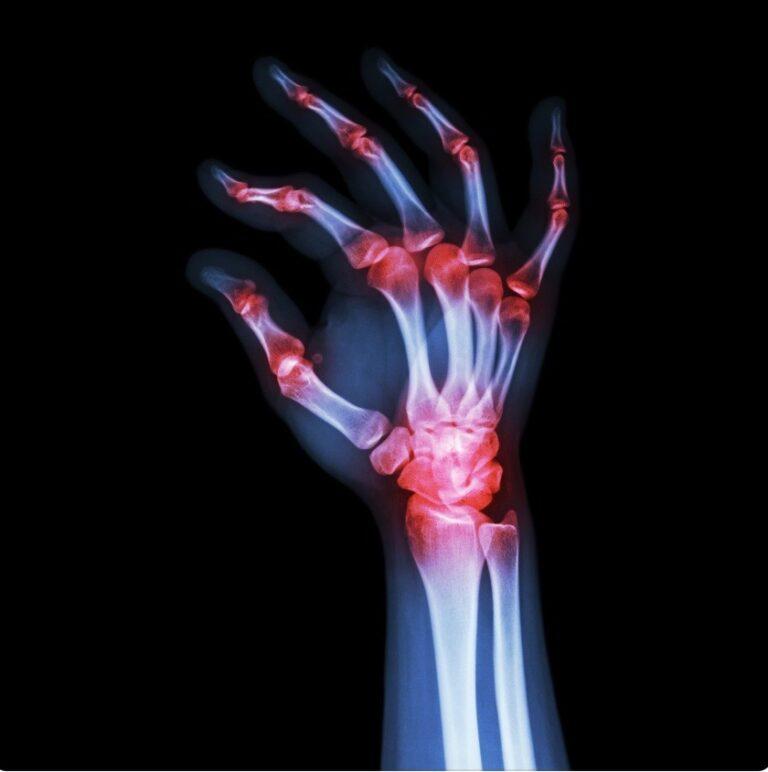

Rheumatoid arthritis is an autoimmune disease that causes chronic inflammation in the joints. It typically affects the small joints in the hands and feet and can progress to larger joints as the disease worsens. Osteoarthritis, on the other hand, is a degenerative joint disease that occurs when the cartilage between the joints wears down over time. It is commonly seen in weight-bearing joints such as the hips and knees.

Imaging studies, including X-rays, CT scans, MRI, and ultrasound, can provide detailed images of the joints and help identify any structural abnormalities or damage. X-rays are commonly used to visualize bone and cartilage loss, while MRI and ultrasound can provide more detailed images of soft tissues and fluid-filled structures near the joints.